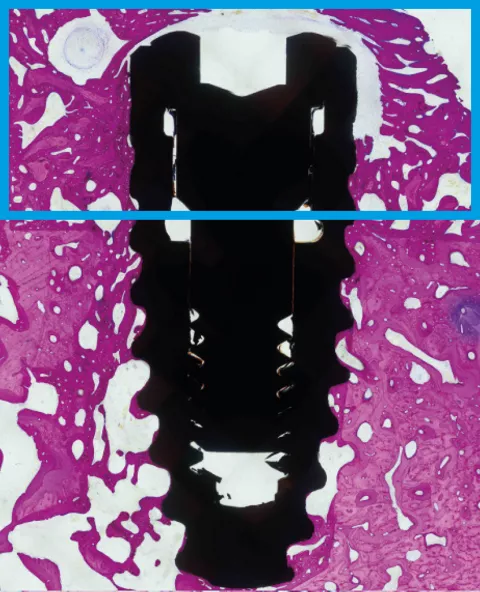

Bone defects can greatly compromise the predictability of osseointegration. In a recent preclinical study22, SLActive® showed significantly higher formation of new bone aggregate within eight weeks compared to the standard Straumann® SLA® hydrophobic surface.

Bone aggregate formation at 8 weeks.22

22 El Chaar E, Zhang L, Zhou Y, et al. Osseointegration of Superhydrophilic Implants Placed in Defect Grafted Bones. International Journal of Oral & Maxillofacial Implants . Mar/Apr2019, Vol. 34 Issue 2, p443-450